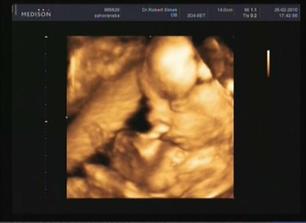

26.01.2010 - kontrola v Gennetu u Dr. Hynka - manžílek zjistil, že místo holčičky se dočká chlapečka, takže teď mu tvář zdobí tak blaženej úsměv :D Je pravda, že mě to trochu zaskočilo, ale už se nemůžem dočkat. .. Takže Ondrášku, ještě 132dní a budeš u nás 🙂 Jinak všechno v pořádku - srdíčko, velikost, váha 320g, stáří 21tt,.... Jinak se máme fajn, už se těšíme na první pohyby 🙂 Další kontrola je na Mělníku za týden ....------------------------------------------------------------------------3. 2. 2010 – desátá kontrola –(podle PM 22+1), AS+, HC (obvod hlavičky) 199 mm/21+6, FAC 171 mm/21+6, BPD 53 mm/22+1, FL (délka stehenní kosti) 37 mm/21+3, váha 464g, obličej bez roštěpu, 4 končetiny, žaludek +, srdce 4 oddíly, bránice +, moč. měchýř naplněn, ledviny + bez dilatace. – No takže vše v pořádku... p.Dr. potvrdila střapeček – takže jsi náš malej chlapeček . Zatím máš asi spoustu místečka v břiše, jelikož tvoje pohyby stále necítím. Občas večer u TV jako by mi něco bublalo v podbřišku, ale kdo ví. Taky máme prodlouženou neschopenku, takže spolu budeme doma v teplíčku a klídku. Zítra teda musím do laborky s močí a krví – jelikož máme bílkovinu v moči, ale snad nic vážného. Další kontrola 3.3.2010. ----------------------------------------------------------------------------------------------------------------